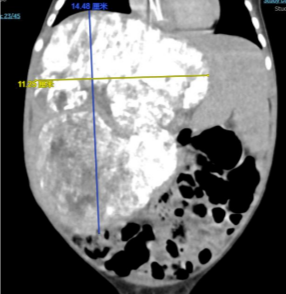

小西宝宝留给我们的第一印象是8个月、6.3kg,瘦骨嶙峋,皮肤菲薄,腹大如鼓,腹壁浅静脉怒张,难以平卧,纳奶费力,饿得饥肠辘辘也只能吃几口奶就能停下来喘几口气。小小的身躯承载着巨大的肿瘤负荷,孩子只能依偎在妈妈的怀抱里才能得到片刻的安眠。

巨大肝母细胞瘤的 - 3.png